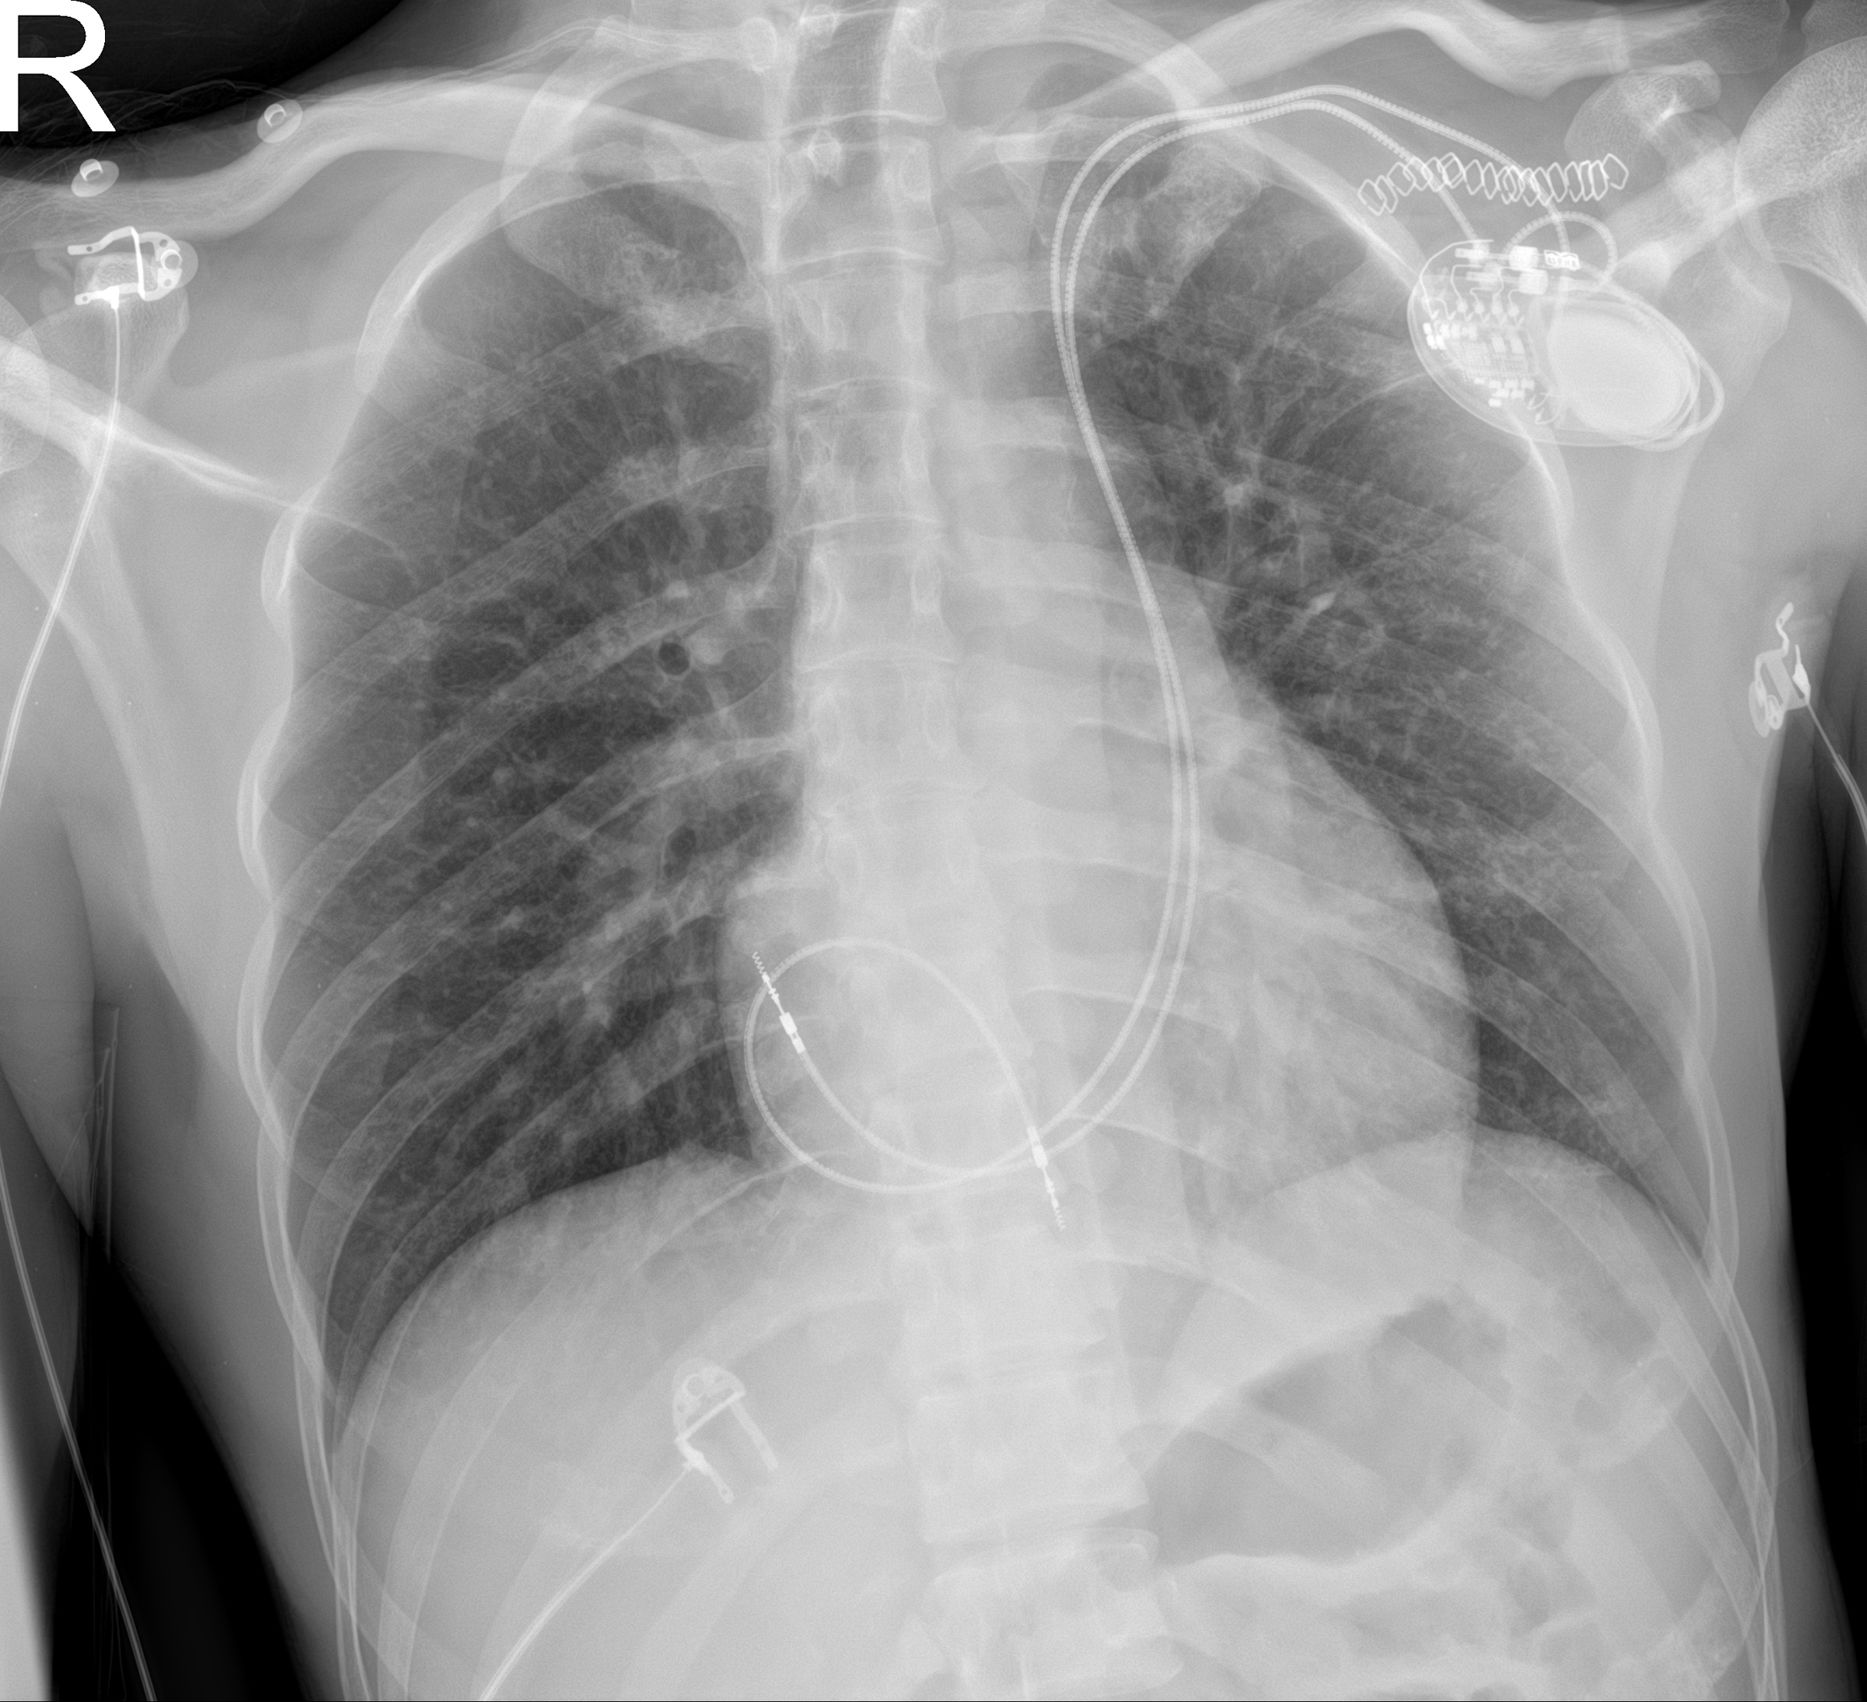

Varón de 31 años con bloqueo bifascicular alternante con bloqueo auriculoventricular completo sintomático con ecocardiograma normal. Se realiza implante de marcapasos definitivo a través de la vena subclavia izquierda, y al introducir la guía metálica se objetiva una vena cava superior izquierda persistente (VCSIP) única, comprobada mediante flebografía y tomografía. La VCSIP desemboca en el seno coronario (SC) y este en la aurícula derecha (AD); se implantaron los electrodos auricular y ventricular derecho (VD) de fijación activa mediante vía retrógrada por el SC (figs. 1 y 2).